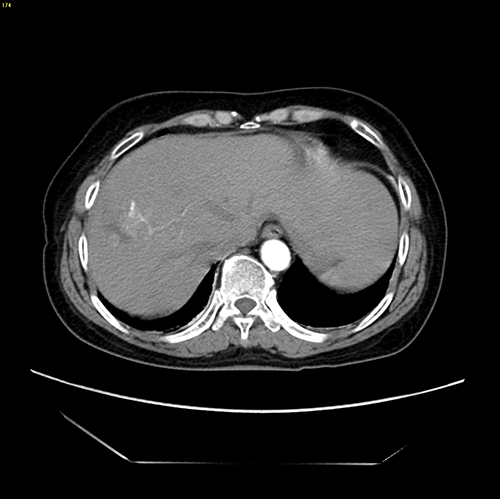

右肝肿瘤----腹腔镜右半肝切除